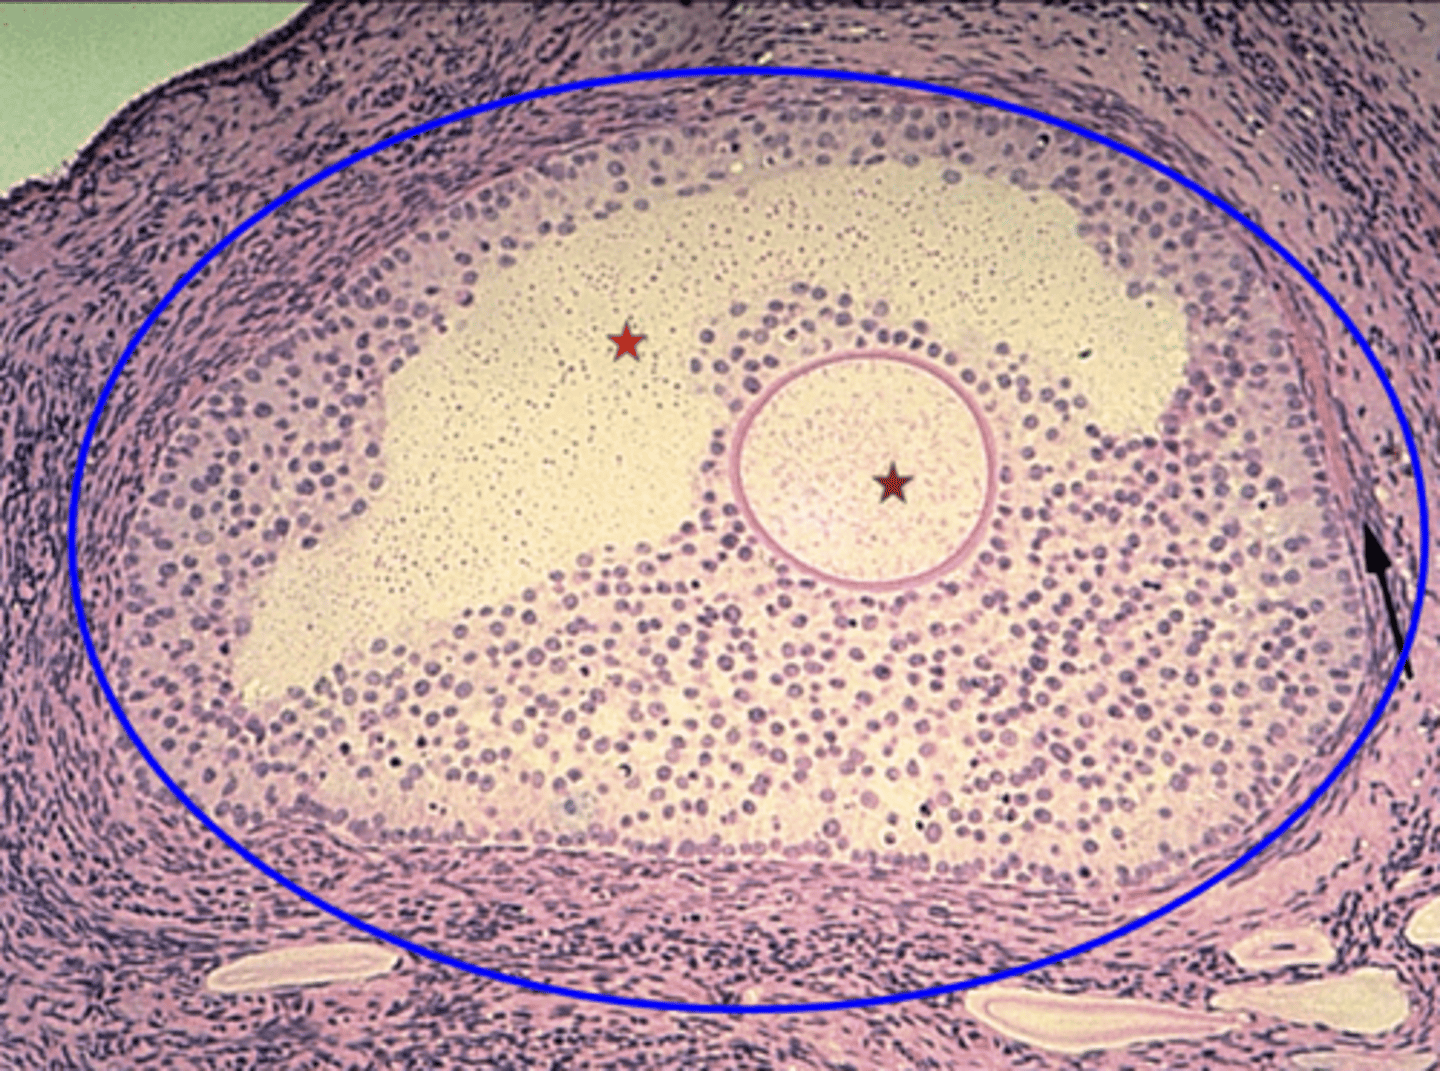

Secondary follicle

What is the blue circle?

Primary oocyte

What is the brown star?

Developing antrum

What is the red star?